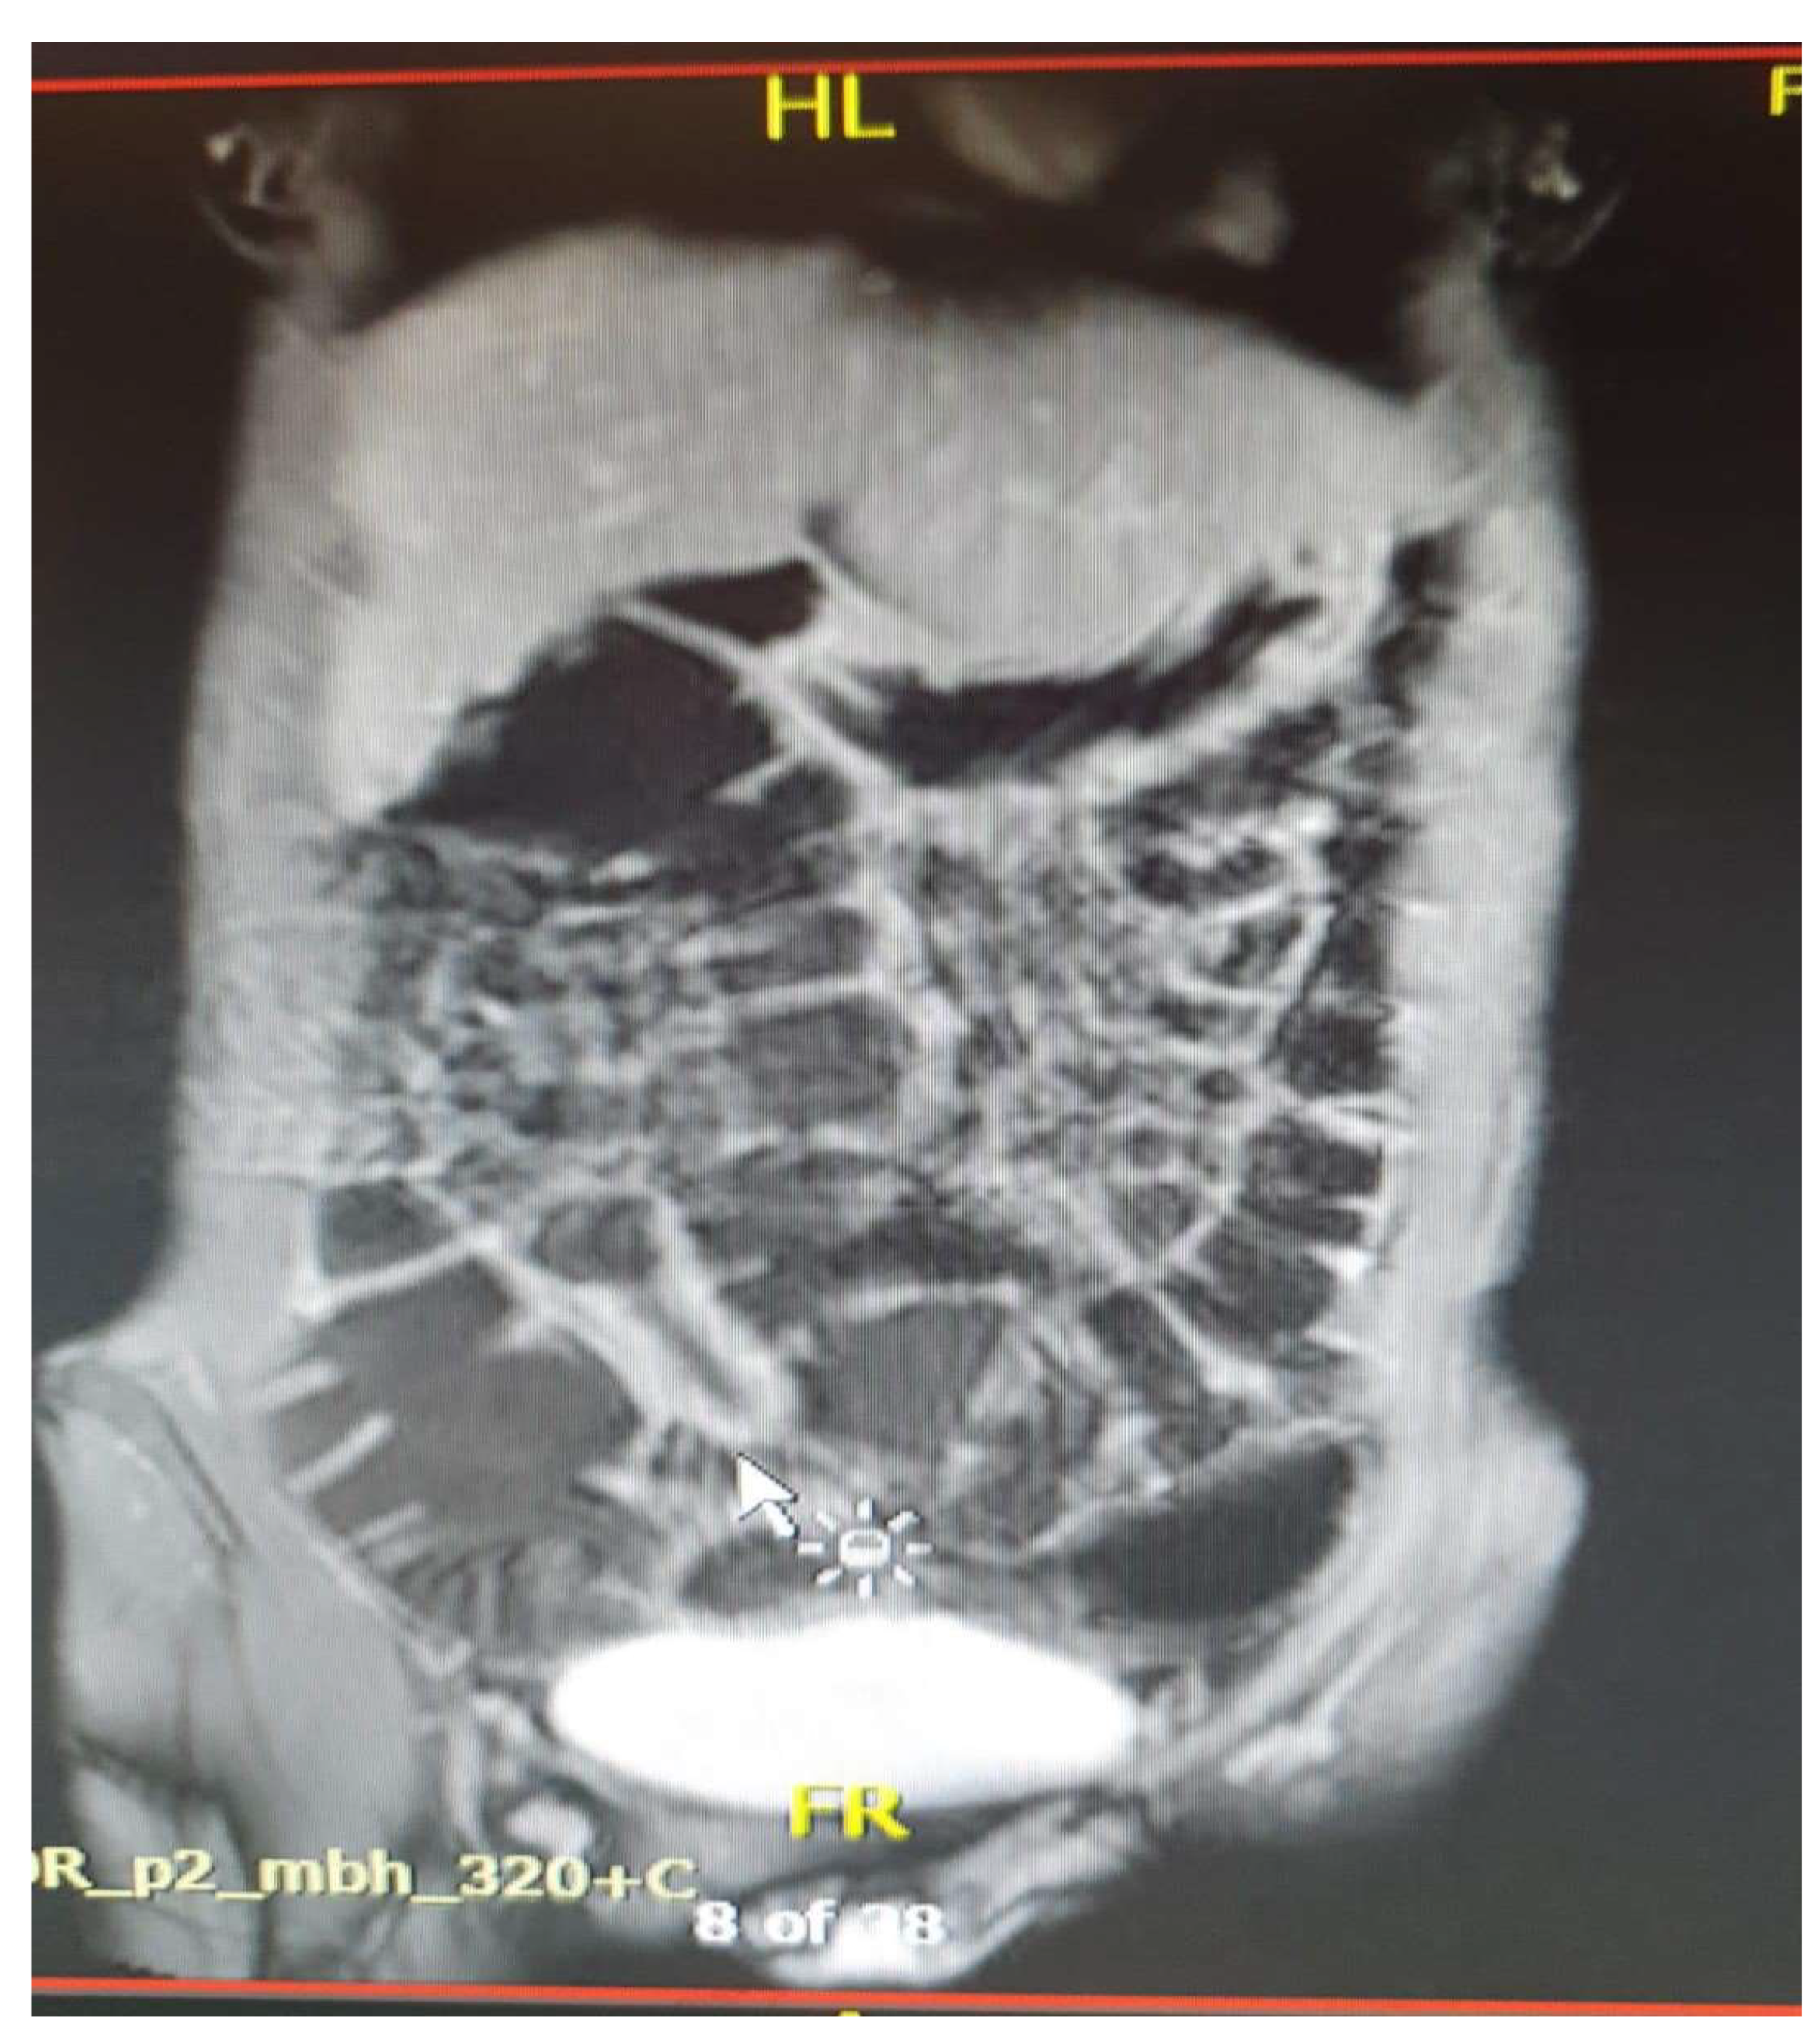

- Magnetic resonance enterography (MRE) has become the gold standard [8] in the evaluation of inflammatory bowel disease, providing simultaneously detailed images of the intestinal wall and adjacent structures and inflammatory lesions [23], differentiating inflammation from fibrosis in both the small and large intestine submucosa and the perineal area [35,36]. MRE also has high accuracy in staging small bowel inflammatory bowel disease [30], in monitoring treatment response and relapse [23], and in detecting and classifying isolated forms of colonic involvement [37]. This imaging modality is preferred in complex cases with evidence of penetrating, fistulizing, and stenosing lesions [23], as well as in fistulas and perianal sepsis [13]. Fat smudging, fecal sign, fluid level, gaseous distension, comb sign (related vascular congestion), and lymphadenopathy are elements mainly visualized/detected by MRE [2]. Another advantage—perhaps the most important—is that MRE is an imaging method that can be used to evaluate the activity of Crohn's disease and ulcerative colitis in both adults and young people [38], without the use of ionizing radiation [2]. Taylor et al. have shown that MRE has a sensitivity of 97% for detecting inflammatory bowel diseases, over 90% for fibro-inflammatory strictures, and specificity of over 95% [30].

- Commonly occurs in active areas of inflammation (Figure 1).

- Requires adequate distension of the small bowel (Figure 4 ).